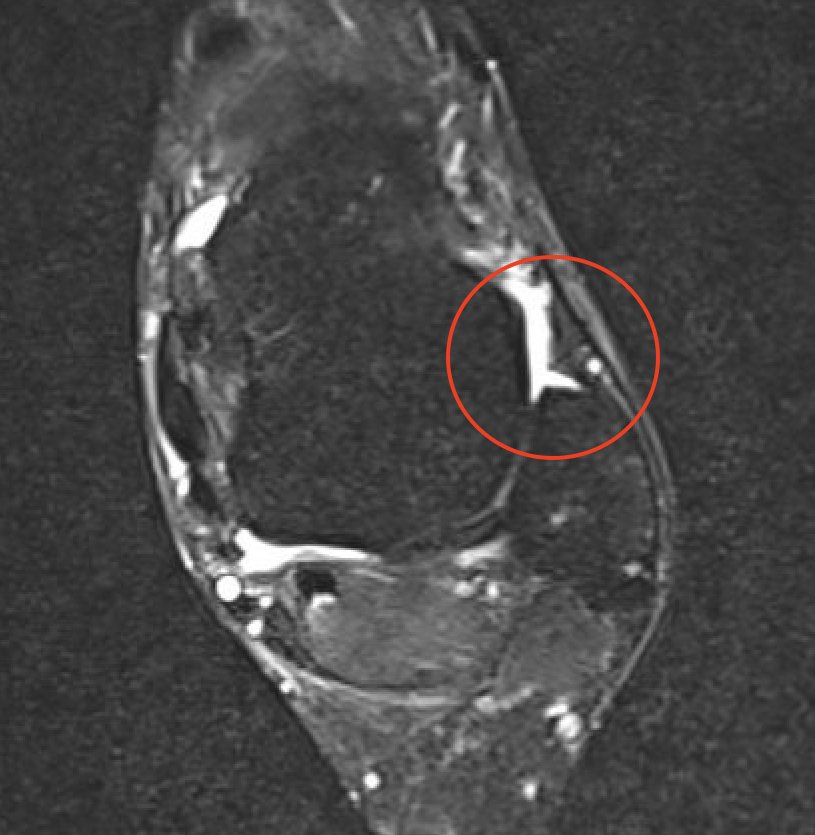

MRI

ATFL tear